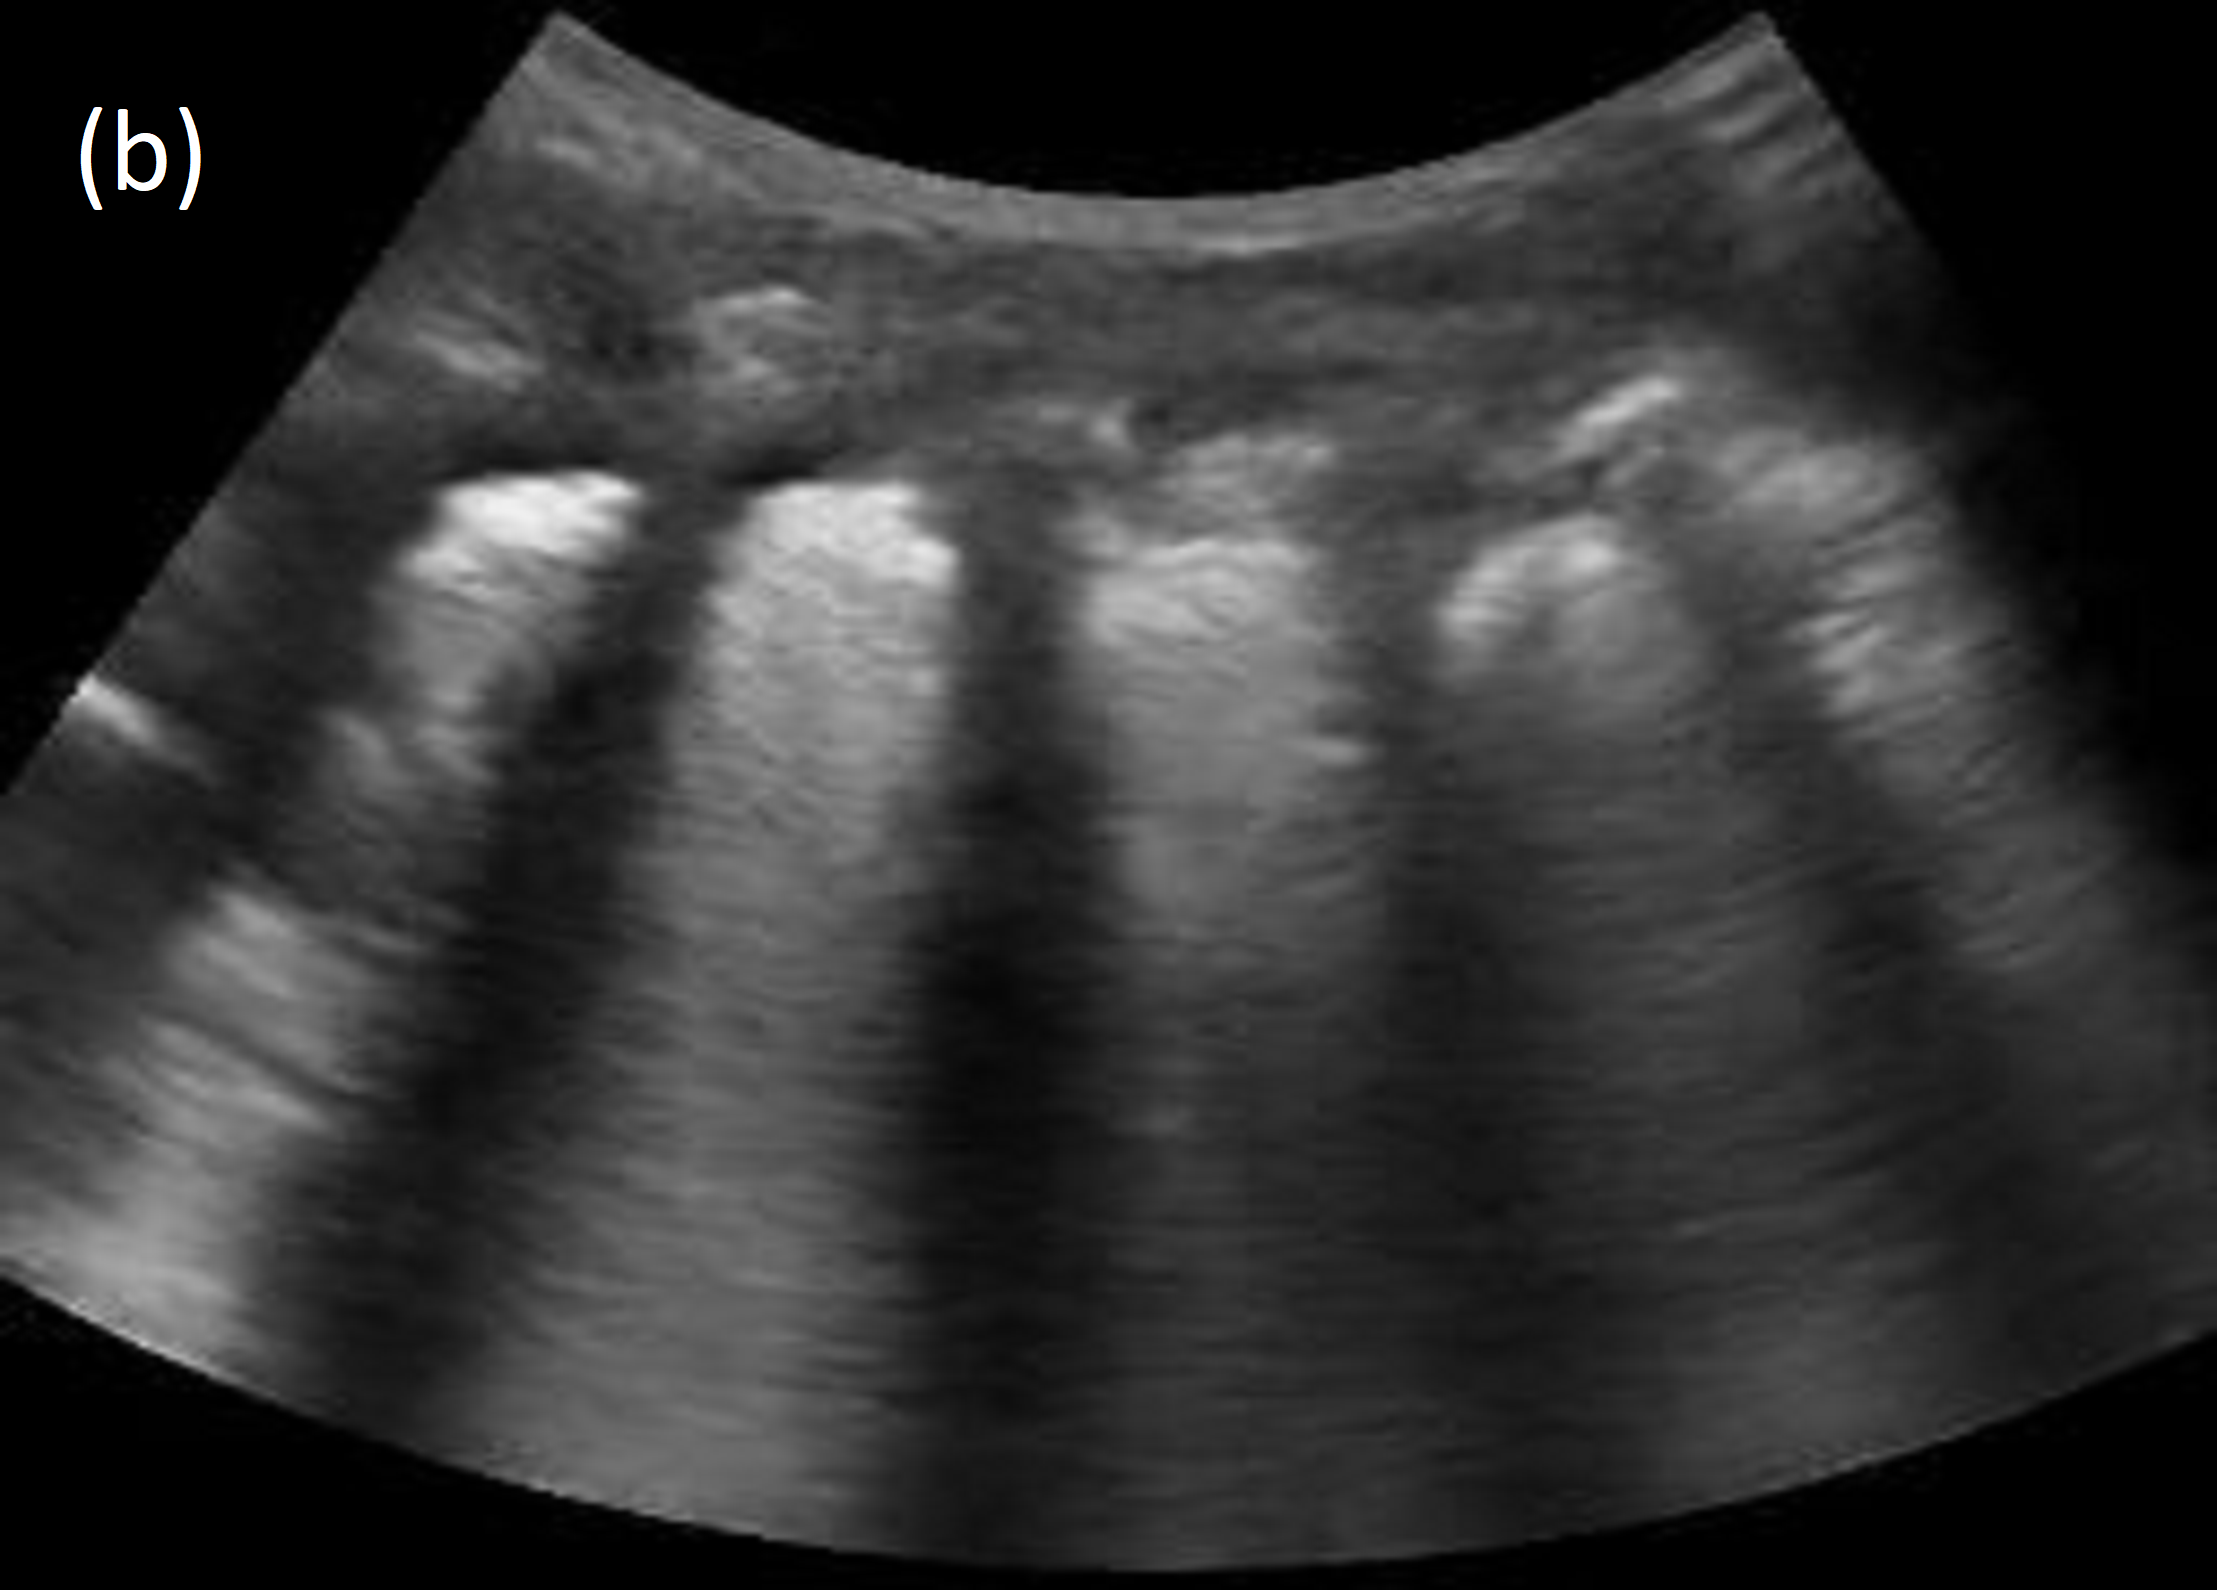

Refer to caption

Figure 1: Consolidation in lung ultrasound. (a) Real consolidation image: infection-induced inflammation causes fluid buildup in the alveoli, presenting as hyper- and hypo-echoic splotches (yellow boxes). (b) Synthetic consolidation image.

Lung ultrasound images largely consist of artifacts generated by acoustic impedance mismatches between lung tissue, fluid, and air. To the trained eye, these artifacts convey information about lung pathologies such as consolidation, which manifests as sub-pleural hyper- and hypo-echoic splotches caused by inflammatory alveolar fluid buildup. See Figure 1. We observe that the synthetic images also display such features and artifacts and preserve the architecture of lung ultrasound images. Figure 3 shows examples of synthetic and real, consolidated and normal, lung ultrasound images. Prominent features of lung ultrasound include the “bat sign” [2] and “rib shadows”, caused by the pleural line and the impenetrability of ribs to ultrasound. These can be observed in the real and synthetic lung images (r1–r4, s1–s4). Pleural lines, A-lines (multiple-echo artifacts of the pleural line) are also present and qualitatively similar in synthetic images (r3, s3). The “shadows” on the left and right sides of images (r1, r2, r4, s1–s4) are caused by poor acoustic contact between the edges of the curvilinear transducer and the child’s body, which is another realistic element of the the synthetic images. Other features of lung ultrasound also appear in synthetic images, such as “hepatization”, caused by excessive fluid accumulation, as seen in (s1, s2). Additional synthetic examples are provided in the supplement.